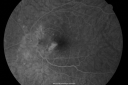

Multifocal Choroiditis and Subretinal Fibrosis - 32 yo Female FA New Lesion OS573 views32-year-old woman vision loss in the right eye associated with macular scarring and multifocal choroiditis in 1999 with new vision loss in left eye: OD 20/400, OS 20/50.

Multifocal Choroiditis and Subretinal Fibrosis - 32 yo Female FA Old Scar OS634 views32-year-old woman vision loss in the right eye associated with macular scarring and multifocal choroiditis in 1999 with new vision loss in left eye: OD 20/400, OS 20/50.